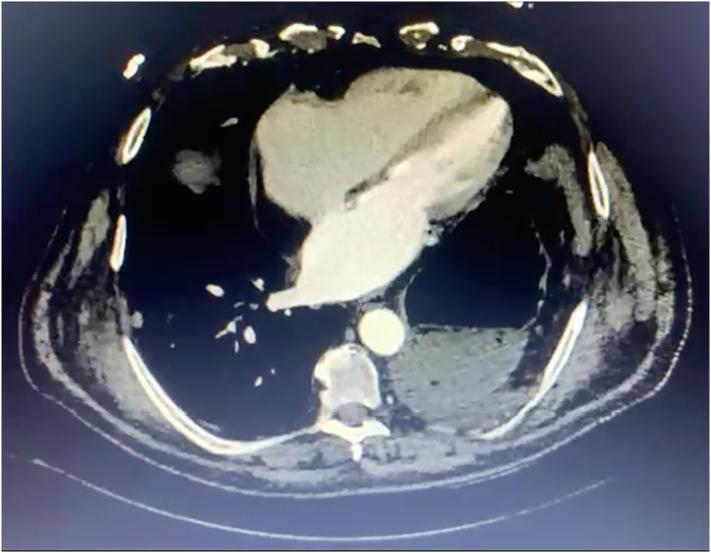

A 75-year-old male with atrial fibrillation with a large hiatal hernia causing clinical decompensation was successfully treated after a laparocopic correction- primary closure of the defect was made with barbed surgical thread plus and placing a biological mesh (porcine small intestine submucosa, non-cross-linked), fixed with cyanoacrylate; after the procedure, he was discharged asymptomatic and with sinus heart rhythm.

一名75岁男性,患有心房颤动,伴有巨大裂孔疝导致临床失代偿,在接受腹腔镜修补术后成功治愈——用带倒刺的手术线进行缺损的一期缝合,并放置生物补片(猪小肠黏膜下层,未交联),用氰基丙烯酸酯固定;术后,他无症状出院,心律为窦性心律。